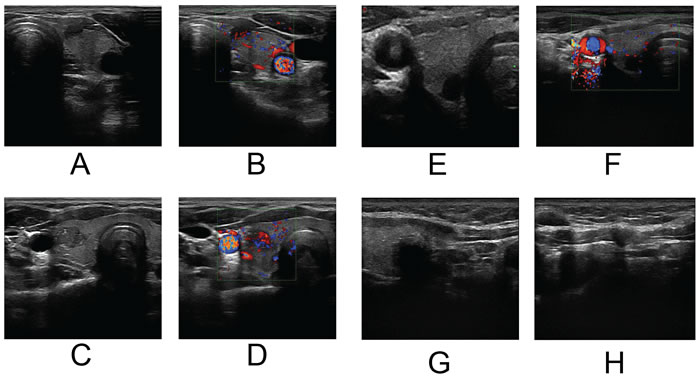

Ultrasound examination of the thyroid was performed with a 5-12 MHz linear array probe. Philips iU22 (Philips Ultrasound, USA) and ESAOTE My Lab 90 (ESAOTE, Italy) ultrasound diagnostic equipment were used for the analysis. Patients were in a supine position, and the anterior neck area was fully exposed. Transverse and longitudinal scanning of each nodule was performed by two radiologists with more than 10 years of experience in thyroid ultrasound. The ultrasonographic features of the thyroid tumors were observed in greyscale. The border (clear/obscure), margin (regular/irregular), shape, peripheral halo, internal architecture (solid/mostly solid), calcification (none/micro/macro), echogenicity, echo homogeneity, lateral shadow (presence/absence), and the degree of capsular contact were recorded. Color-Doppler ultrasound was also included to analyze the blood flow (none/ low/medium/high) and vascularity (none/circular/central/mix) of the nodules. In patients with multifocal tumors, the most suspicious nodule was analyzed. (Figure 5)

Figure 5: A.&B. A hypoechoic tumor on the left lobe with an irregular margin and 25~50% capsular abutment. Color-Doppler showed central vascularity with medium blood flow. LNM in the left central compartment was detected by ultrasonography while pathology showed no cervical LNM. C.&D. An isoechoic tumor on the right lobe with an irregular margin and microcalcification. Color-Doppler showed mixed vascularity with high blood flow. LNM in both left and right central compartment was detected by ultrasonography while LNM only on the right side was confirmed by pathology. E.&F. A markedly hypoechoic tumor on the right lobe with an irregular margin and low blood flow. No suspected LNM was detected by ultrasonography while LNM in the right central compartment were diagnosed by pathology. G.&H. A hypoechoic tumor on the right lobe with an irregular margin. LNM in the right central compartment was detected by ultrasonography while pathology confirmed LNM in both the left and right central compartments.